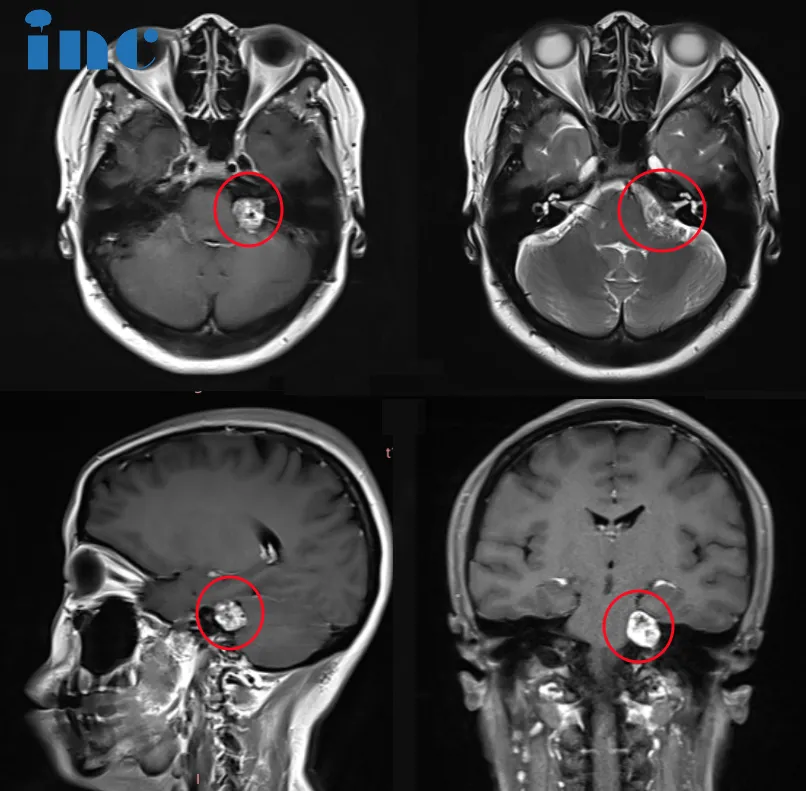

直至2023年7月,症状急剧加重,表现为左侧头皮、脸颊及舌部的持续性麻木,伴随剧烈耳痛,经检查最终确诊为左侧听神经瘤。影像学提示肿瘤已导致轻微脑干受压、三叉神经受累及听力障碍。鉴于肿瘤全切手术难度极高,术中稍有不慎即可能导致面瘫或失聪,这对于常年从事人际交往工作的吴女士而言,无异于陷入绝望境地。

2023年11月1日,手术如期进行,由巴特朗菲教授主刀,北京天坛医院专家团队密切配合。术中,巴教授娴熟的操作技巧与神经电生理监测团队的精准护航相结合,确保了肿瘤被完全切除的同时,最大程度地保护了面神经与听神经的功能。术后第一天,吴女士即转入普通病房,意识清醒,对答如流。“耳朵能听到声音,面部可以做表情,麻木感也消失了”,术前的所有担忧彻底消散。

术后影像学对比显示:肿瘤获得完全切除,未出现新的神经功能损伤,术前听力得以保留,面神经功能完好无损。